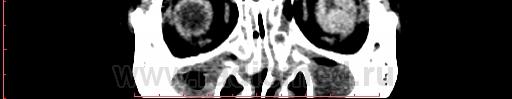

КТ орбит. Образование левого глазного яблока

Женщина 57 лет обратилась с жалобами на снижение зрения левого глаза. На УЗИ объемное образование левого глаза. Написал DDs меланома, ретинобластома.

Меланома - да, надо исключать. (наиболеее вероятно).

Рентинобластома - крайне маловероятна (после 5-ти лет эта опухоль практически не встречается).

Я тоже склоняюсь больше в сторону меланомы. Ретинобластома врожденная опухоль, в 90% случаев диагностируется как вы и сказали до 5 лет, у взрослых встречается редко и в 95% содержит обызвествления, но в дифф.ряд указал на всякий случай.